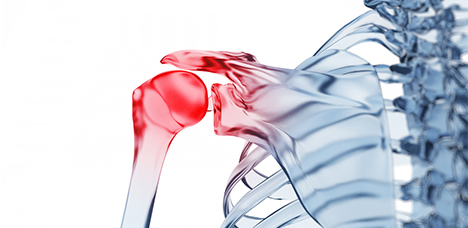

어깨 관절 부위 주요질환

오십견

어깨가 얼어버린 것처럼 모든 방향으로 움직일 수 없고, 오랜 기간 통증이 지속

회전근개 손상

어깨회전근 힘줄에 염증이 생긴 질환

이두근 건염

상완이두근의 힘줄에 염증이 생기는 질환